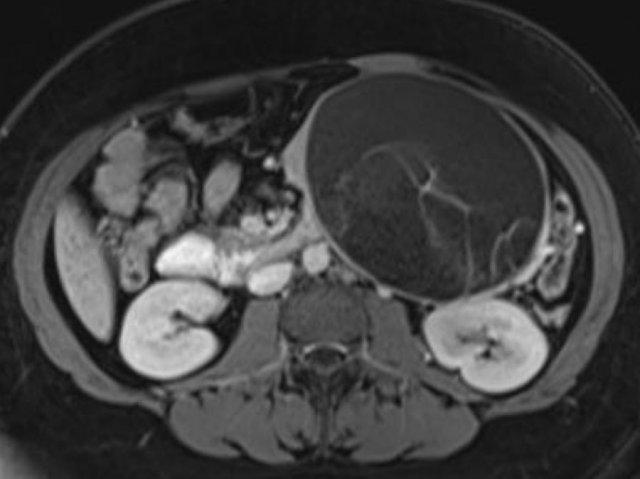

Hình ảnh CT của bệnh nhân nữ 46 tuổi với triệu chứng đau bụng phải mơ hồ.

Các đặc điểm hình ảnh bao gồm:

- Nang có vách ngăn kích thước 7 cm ở đầu tụy.

- Vỏ nang nhẵn.

- Không có thùy hóa (lobulation).

- Không thông với ống tụy chính.

MRI cho thấy nang có vách ngăn ở đầu tụy kích thước 7 cm với vỏ nang nhẵn, không có thùy hóa và không thông với ống tụy chính.

Kết quả phẫu thuật xác nhận u nang tuyến nhầy độ thấp (low grade mucinous cystadenoma) có mô đệm buồng trứng (ovarian stroma).